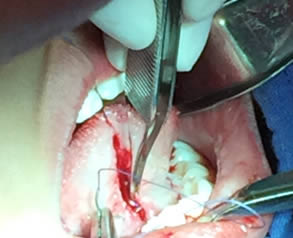

• Se eliminó el frenillo en su totalidad  con la ayuda de tijeras iris recta y hoja de bisturí del No. 15 así como todo el tejido residual fibroso correspondiente al frenillo. Se realizó genioplastia con pinza de mosco y disección roma para liberar adecuadamente la inserción frénica hasta la cara lingual de los incisivos inferiores. (Figuras  7, 8 y 9)

Figuras 7 y 8. Eliminación total del frenillo y genioplastia

Figura 9. Resultado obtenido después de genioplastia